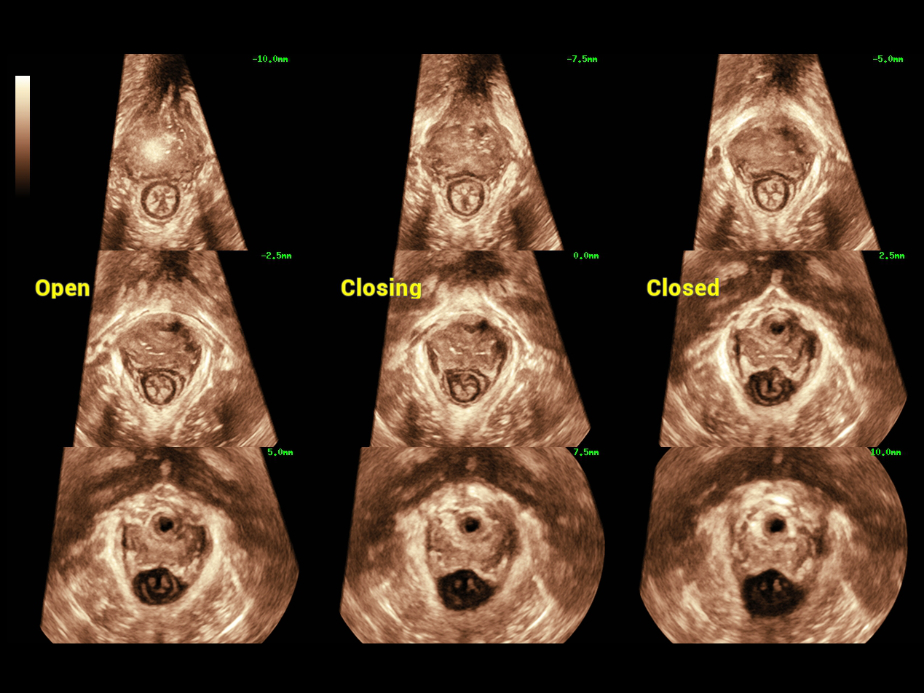

Die Verwendung von Ultraschall im Bereich der Urogyn?kologie findet unter ?rztinnen und ?rzten zunehmend Beachtung. Sie kann die Diagnose der weiblichen Beckenbodendysfunktion (FPFD) sowie pr?- und postoperative Evaluationen erleichtern.

Bei der FPFD-Prognose mittels Ultraschall verfolgen ?rztinnen und ?rzte einen globalen Ansatz, der die umfassende, akkurate Diagnose der vorderen, mittleren und hinteren Teile des Beckens vorsieht, mit einer gro?en Zahl dafГјr n?tiger 2D-Messungen, 3D-/4D-Bildgebung und Evaluationen usw. Die Untersuchung ist zeitaufwendig und unangenehm, was hohe Anforderungen an die Bildgebungsmodi und die Messgeschwindigkeiten stellt.

Nuewa bietet automatische 2D-Vermessungen der Beckenabschnitte sowie ein intelligentes Volumenberechnungssystem, einschlie?lich automatisierter Berechnung des Hiatus Levatorius und der Analyse mehrerer Abschnitte.